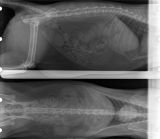

radiographie de gestation chienne

Radiographie de gestation